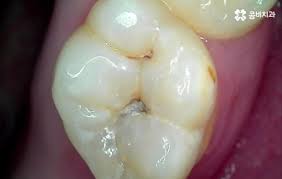

2. 증상 체크: 이렇게 깨졌다면 조심!

- 🦷 부분 깨짐: 일부가 떨어져 이물감

- 🦷 금이 간 경우: 통증·민감도 증가 가능

씹을 때 통증, 푹 꺼지는 느낌 등이 느껴진다면 크라운 손상 가능성을 의심해야 합니다. 특히 신경치료한 치아가 노출되었다면 즉시 치과를 방문해야 합니다.